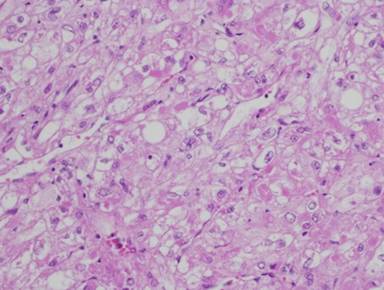

Pathological analysis of the specimens revealed a well-circumscribed vascularized neoplasm, measuring 32x27x30 mm, composed of epithelioid smooth muscle cells with clear cytoplasm rich in glycogen (Figure 1). The tumor exhibited immunoreactivity to alpha-smooth muscle actin (Figure 2) and to melanoma-associated antigen HMB-45 (Figure 3), but not to the epithelial marker, cytokeratin. The tumor displayed high nuclear pleomorphism but no mitotic figures were seen in 50 high power fields (HPF) and the proliferative index Mib1 (Ki67) was less than 1%. No tumor was detected at the surgical margins or in the 14 regional lymph nodes resected.

Figure 1. Well-vascularized neoplasm composed of epithelioid smooth muscle cells with clear cytoplasm rich in glycogen (magnification x200). |